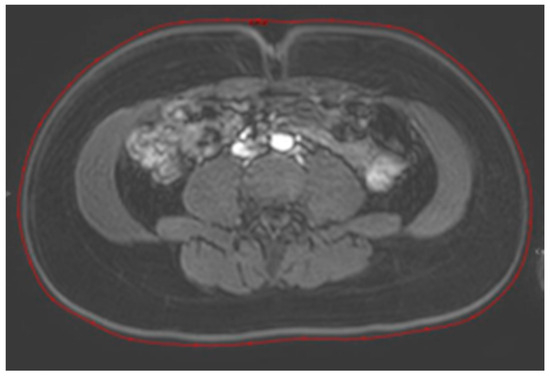

2.2. Image Acquisition and Endpoints